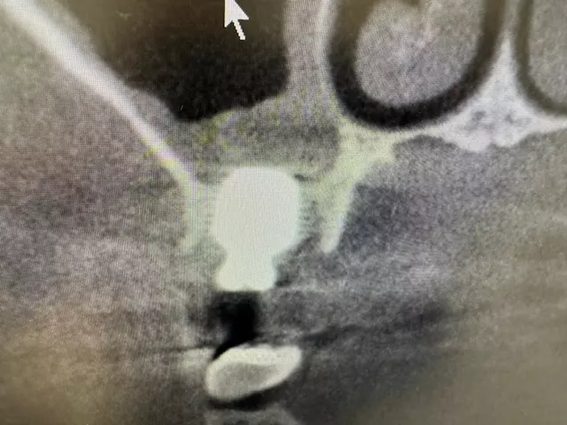

| 主訴 | 左上5番部インプラント埋入 |

| 治療内容 | 隔壁を傷つけないようドリリング後、隔壁部分も利用しつつソケットリフト。骨補填後埋入。ISQ値60 トルク値35N程度。もともと歯が無い部位にインプラント希望。 |